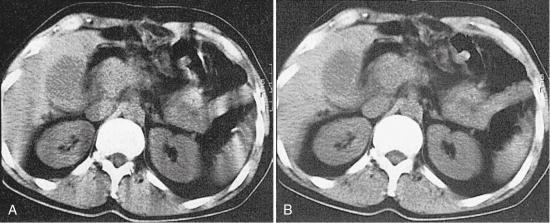

Ever since its introduction in 1990, single-slice volume CT has been used successfully in many body CT imaging applications in which speed and volume coverage are important. Volume coverage and speed can be increased by using higher pitch ratios; however, higher pitch ratios in single-slice volume CT scanning degrade image quality (z-axis resolution) and produce image artifacts. In SSCT, the volume coverage speed is limited, especially in clinical applications that demand large-volume scanning with critical timing requirements and optimum image quality (z-axis resolution and low image artifacts), such as CT angiography with 3D, multiplanar reformatting or reconstruction (MPR), and maximum intensity projection (MIP) techniques (Hu, 1999). Single-slice volume CT is based on the use of a single row of detectors (1D detector array). Because the x-ray beam is highly collimated to the size of the detector array, only a small percentage of x-rays emitted by the tube is used in the imaging process. This situation is described as poor geometric efficiency. Also, SSCT uses the 360-degree linear interpolation algorithm (LIA) and the 180-degree LIA to improve the problems imposed by the 360-degree LIA, such as poor image quality and artifact production. However, the 180-degree LIA produces more noise while preserving the detail (slice sensitivity and spatial resolution). Additionally, the time duration for covering defined volumes in SSCT (several seconds) is limited by several factors, such as the ability of some patients, particularly those who are critically ill, to maintain a single breath-hold during volume scanning and the heat loading of the x-ray tube.

SSCT is also limited in its ability to meet the needs of time-critical clinical examinations such as multiphase organ dynamic studies and CT angiography, in which both arterial and venous phases are extremely important, with smaller amounts of contrast media. The use of higher pitch ratios to solve these problems degrades the slice sensitivity profile (detail). Therefore, other methods are needed to overcome these limitations to improve the performance of SSCT in terms of better use of the x-ray output (improved geometric efficiency) and scan parameters affecting image quality and volume coverage.